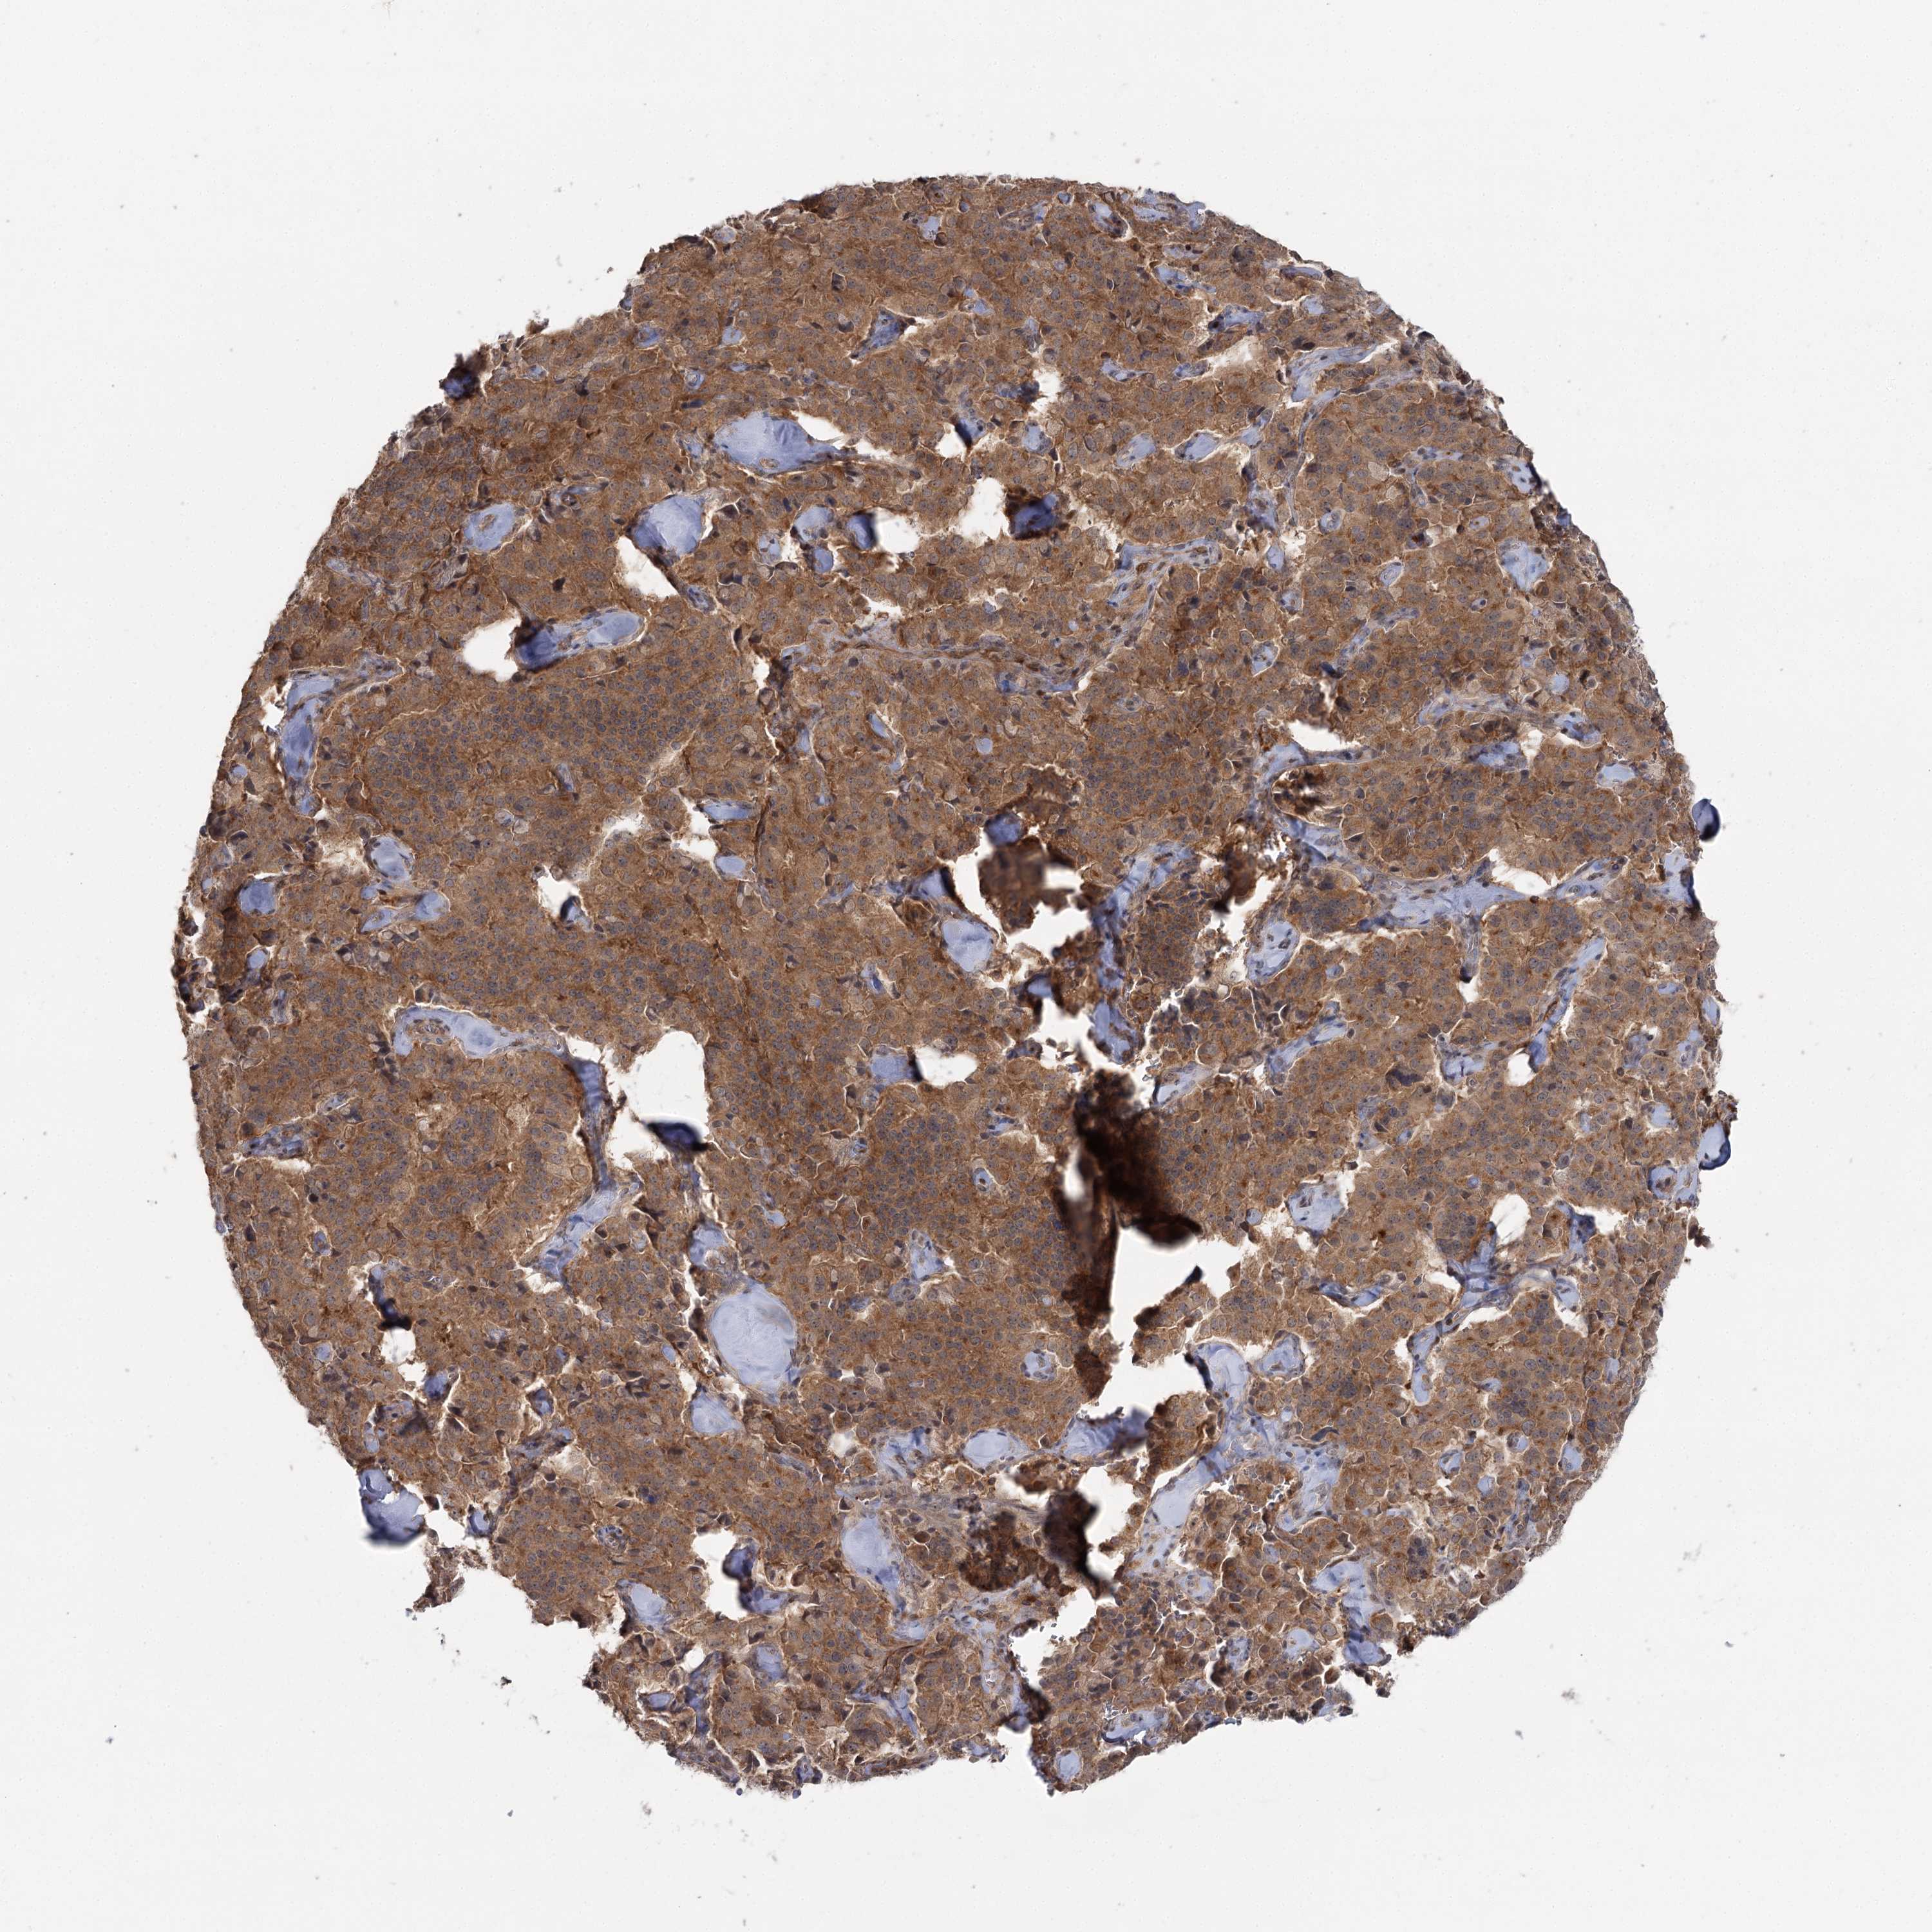

PANCREATIC CANCER - Protein expressioni

A mouse-over function shows sample information and annotation data. Click on an image to view it in a full screen mode. Samples can be filtered based on level of antibody staining by selecting one or several of the following categories: high, medium, low and not detected. The assay and annotation is described here.

Note that samples used for immunohistochemistry by the Human Protein Atlas do not correspond to samples in the TCGA dataset.

Antibody stainingi

Antibody staining in the annotated cell types in the current human tissue is reported as not detected, low, medium, or high, based on conventional immunohistochemistry profiling in selected tissues. This score is based on the combination of the staining intensity and fraction of stained cells.

Each image is clickable and will lead to virtual microscopy that enables deeper exploration of all samples and also displays staining intensity scores, fraction scores and subcellular localization as well as patient and tissue information for each sample.

Antibody HPA038084

Staining

High

Medium

Low

Not detected

Intensity

Strong

Moderate

Weak

Negative

Quantity

>75%

75%-25%

<25%

None

Location

Nuclear

Cytoplasmic/membranous

Cytoplasmic/membranous,nuclear

Adenocarcinoma, NOS